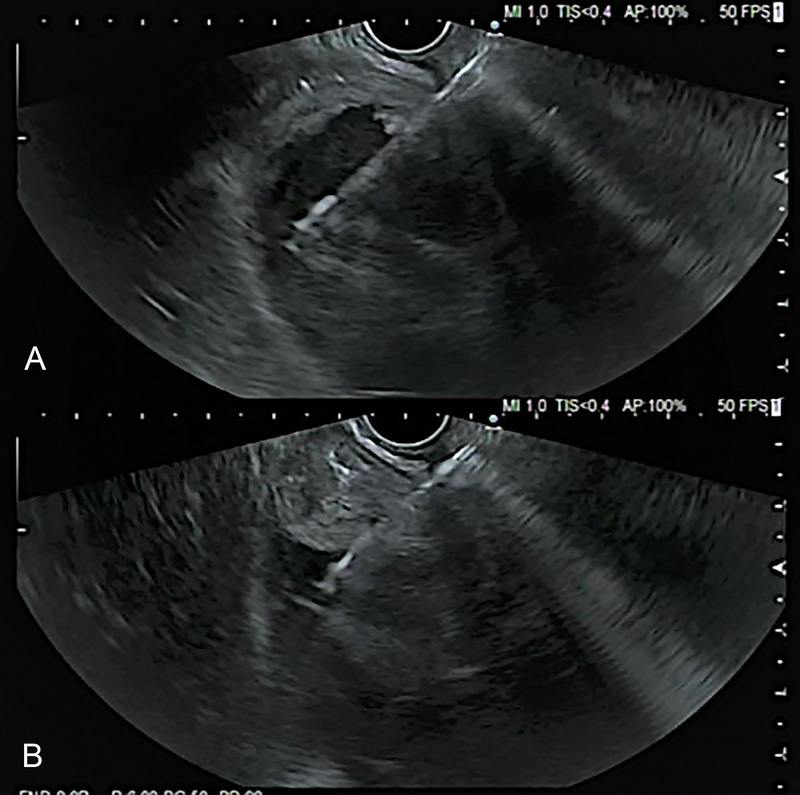

EUS-guided aspirate of a traumatic paraduodenal duodenal hematoma with gastric outlet obstruction (with videos).

eus引导下的外伤性十二指肠旁血肿伴胃出口梗阻的抽吸术(附录像)。